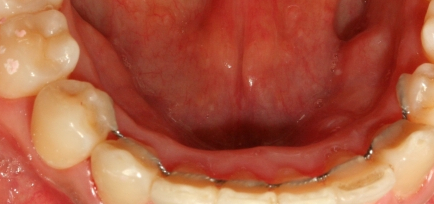

위에서 보았을 때 튀어나온 앞니가 들어간 사실을 확인할 수 있고요

이때 안쪽으로 들어가 있는 철사는

교정이 끝나면 하는 유지 장치 중 하나입니다.

교정이 끝나고 나서도 틀어지지 않도록 유지해 주는 장치입니다..